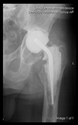

A 3D pelvis reconstruction allowed further processing using the Mimics Innovation Suite (Materialize NV, Leuven, Belgium), which is an engineering software package that enables 3D medical imaging and surgical-related planning. So, the design of the patient-specific aiming device was based on a 3D reconstruction of the patient’s own anatomy. After importing and transforming the two-dimensional Digital Imaging and Communications in Medicine (DICOM) standard file, the radiation absorption range was selected using the windowing method for spatial imaging of the reliable bone structure (Figure 1).

Figure 1.

3D images of the mask that appeared when the CT scans were threshold and the spatial model derived from it. The heads of the implanted screws are displayed in purple.

The default threshold window ranges from 200 to 2000 HU according to the Hounsfield scale, modified to consider the parameterization of the recordings and the specific density of the selected bones.

The selected range is immediately displayed on the screen so that the consequence of the change in the threshold values can be immediately evaluated on the CT slice images in the form of a colored highlight.

The mask obtained in this way contained only the real bone volume relevant to the task, in our case, the pelvis with significant bone defects and the femur on the same side.